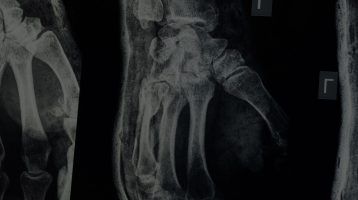

Diagnosed with osteoporosis or not, maintaining strong bones is crucial for our health, especially as we age. Regular exercise and resistance training is recommended to prevent the onset of, and reduce symptoms of osteoporosis, as it can help increase bone density, improve balance, and prevent osteoporosis-related fractures.

Whether you’ve been diagnosed with osteoporosis or not, maintaining strong bones is crucial as we age. Healthy, strong bones will prevent falls, fractures and keep your muscles and overall health in good shape. This article introduces how exercise has a positive effect on stimulating an increase of bone density and can decrease your risk of osteoporosis.